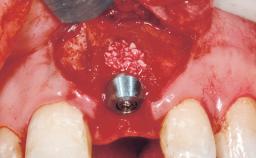

Late Placement of an Implant in a Maxillary Left Central Incisor Site

A 36-year-old female patient was referred for the replacement of the upper left central incisor (tooth 21), which had fractured. Although the tooth had been asymptomatic for many years, the crown began to loosen, at which time she presented to her dentist for an assessment. Teeth 21 and 22 had both been endodontically treated many years previously. She was a healthy individual and a non-smoker.

On examination, the patient had a low lip line and only displayed the coronal half of the anterior teeth when smiling.

The crown of tooth 21 was splinted to the adjacent teeth with composite resin, and the gingiva was inflamed.